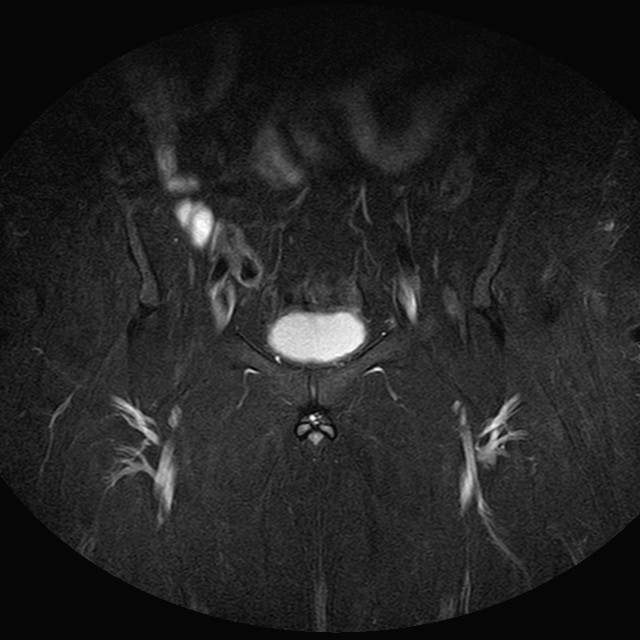

Esami: RMN BACINO

eSTIR

Evidenti e simmetriche alterazioni osteofitosiche in regione coxo femorale con riduzione delle rime articolari. Degenerazione completa del cercine glenoideo. Non attuali segni di versamento articolare. Non segni di edema osseo che escludono attuale algodistrofia od osteonecrosi. Lieve e simmetrica riduzione del trofismo della muscolatura glutea.